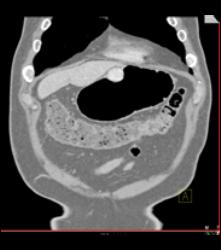

Glomus Tumor